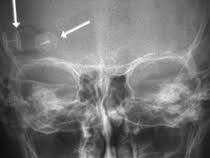

Orbitachirurgie Und Tumoren Mit Sehnervenkompression Neuroonkologisches Zentrum Clemenshospital Munster